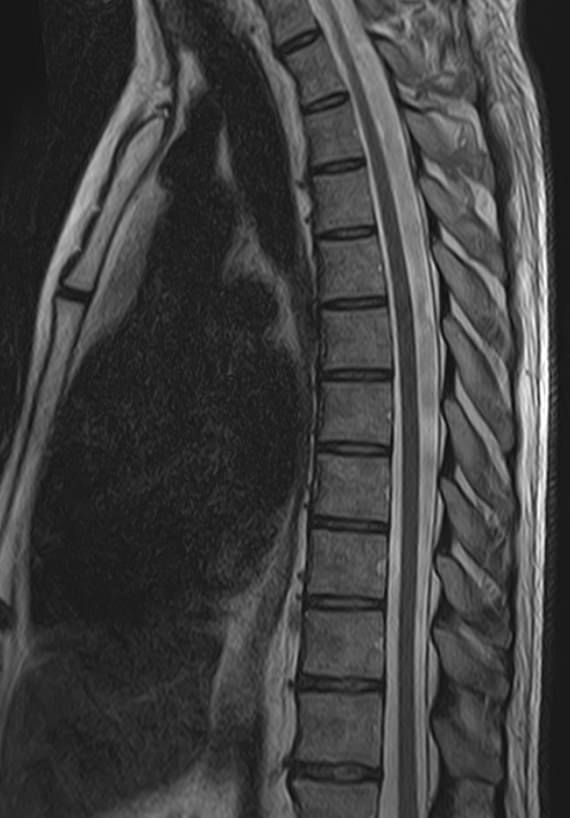

Магнитно-резонансная томография является современным, высокоточным, неинвазивным и безболезненным методом диагностики различной патологии позвоночного столба. Благодаря МРТ можно визуализировать костную структуру позвонков, оценивать состояние спинного мозга на исследуемом уровне, нервных корешков, связочного аппарата и окружающих мягких тканей. В основе метода лежит использование внешнего магнитного поля, которое не оказывает негативного влияния на организм человека. Отсутствие использования ионизирующего излучения делает МРТ безопасным методом исследования и позволяет проводить его достаточно часто по мере необходимости.